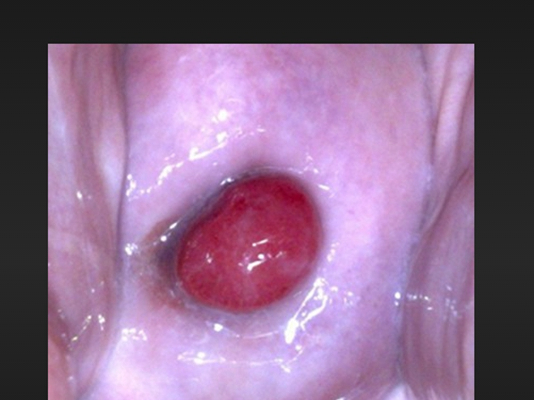

子宮頸糜爛圖片

宮頸糜爛 (8)

宮頸糜爛 (9)

宮頸糜爛 (56)

宮頸糜爛 (57)

宮頸糜爛 (58)

宮頸糜爛 (59)

宮頸糜爛 (6)

宮頸糜爛 (60)

宮頸糜爛 (7)

宮頸糜爛 (40)

宮頸糜爛 (41)

宮頸糜爛 (42)

宮頸糜爛 (43)

宮頸糜爛 (44)

宮頸糜爛 (45)

宮頸糜爛 (46)

宮頸糜爛 (47)

宮頸糜爛 (48)

宮頸糜爛 (49)

宮頸糜爛 (5)